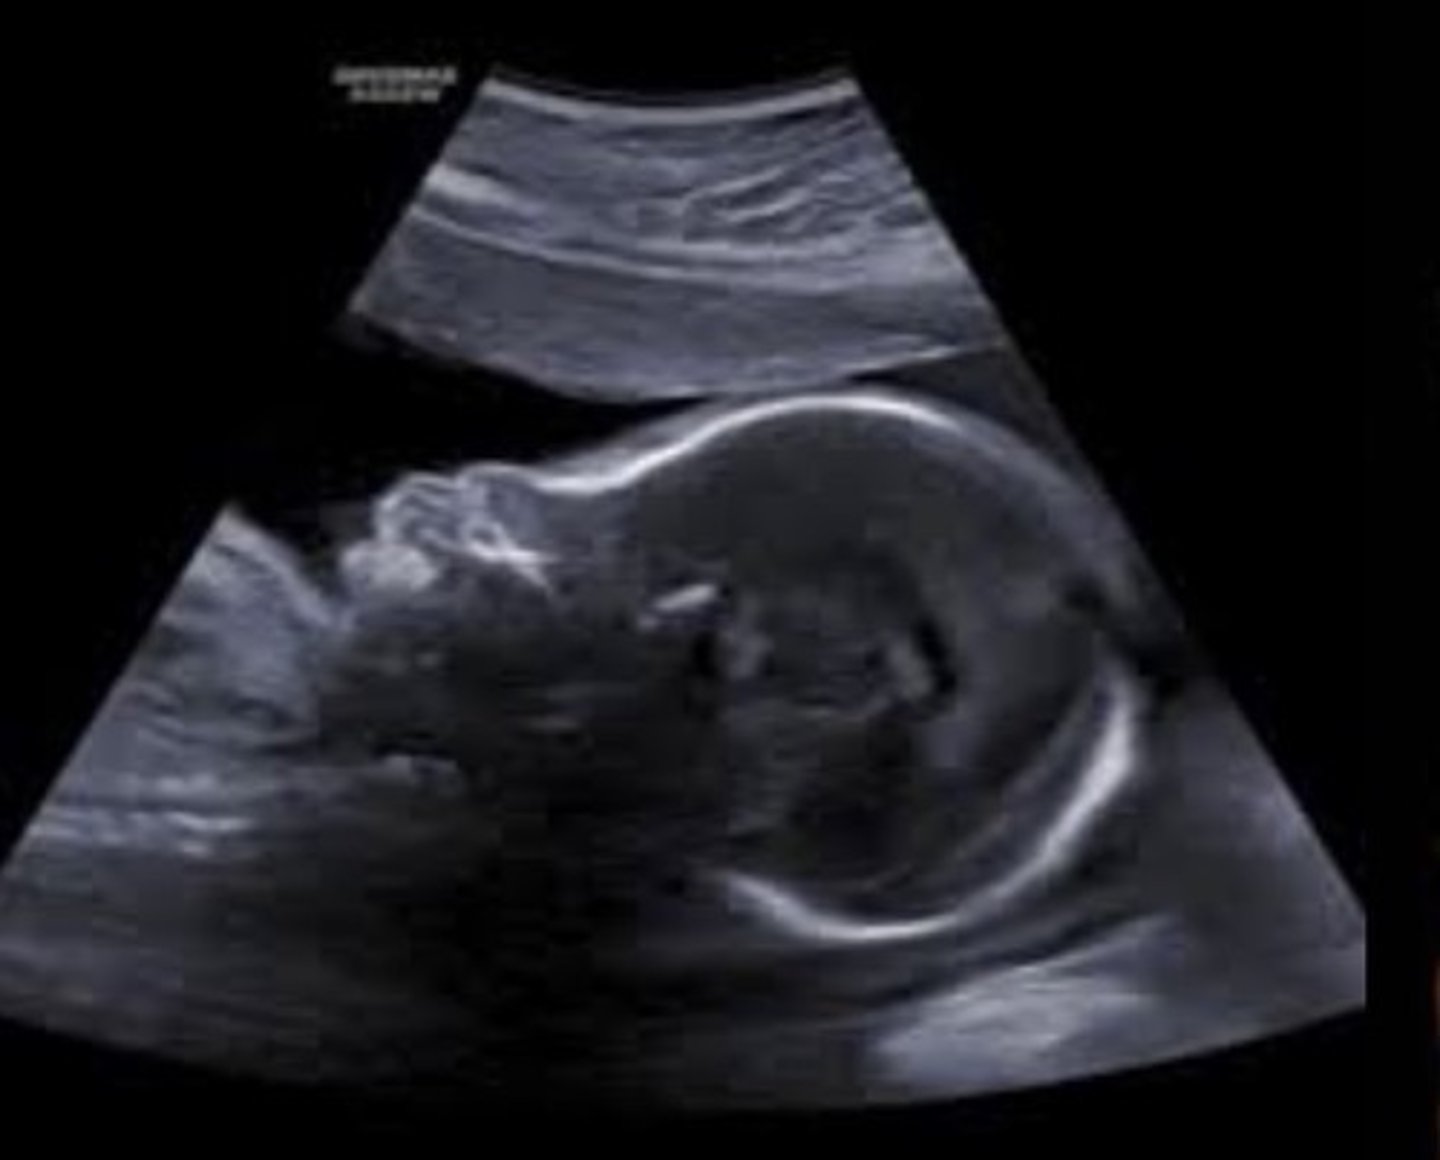

Caudal Regression

Incomplete development of lower half of body

Sacral agenesis

Talipes - cubed feet

Short lower extremities

Sacrococcygeal Teratoma

Large complex mass

Arises from sacral spine